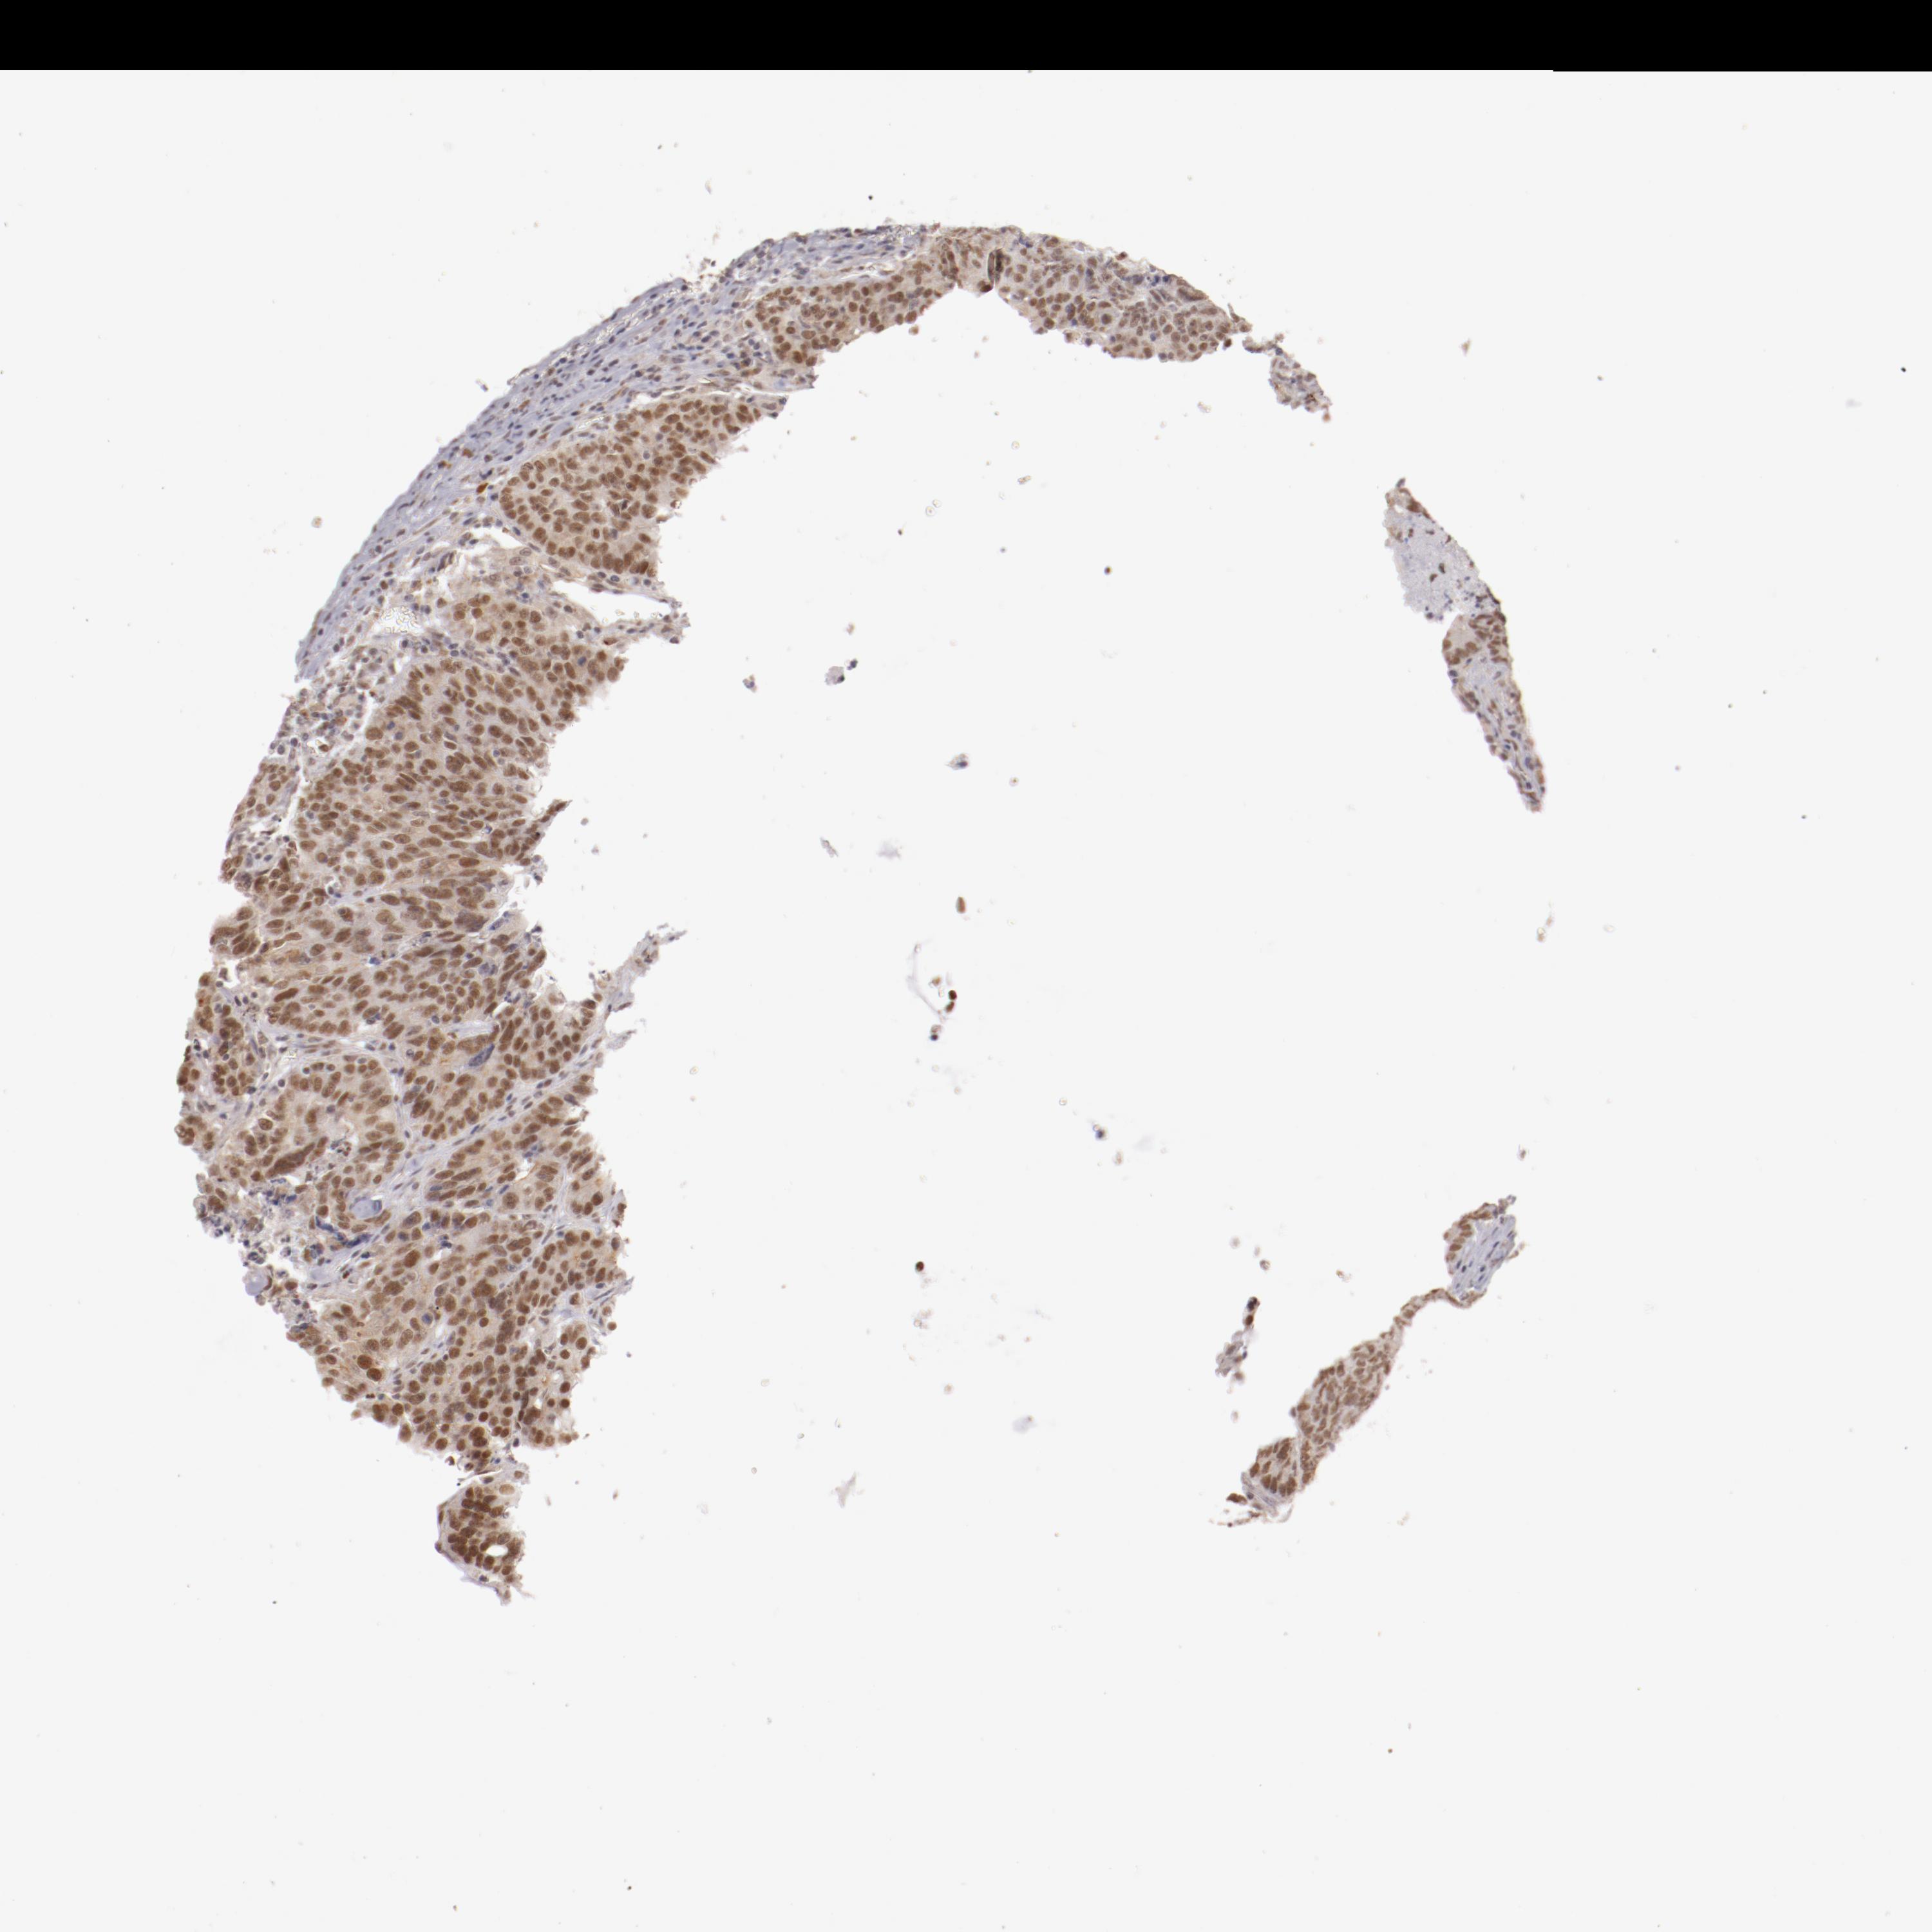

CANCER COLORECTAL CANCER Show tissue menu

Colorectal cancer

Human cancer

Colon adenocarcinoma